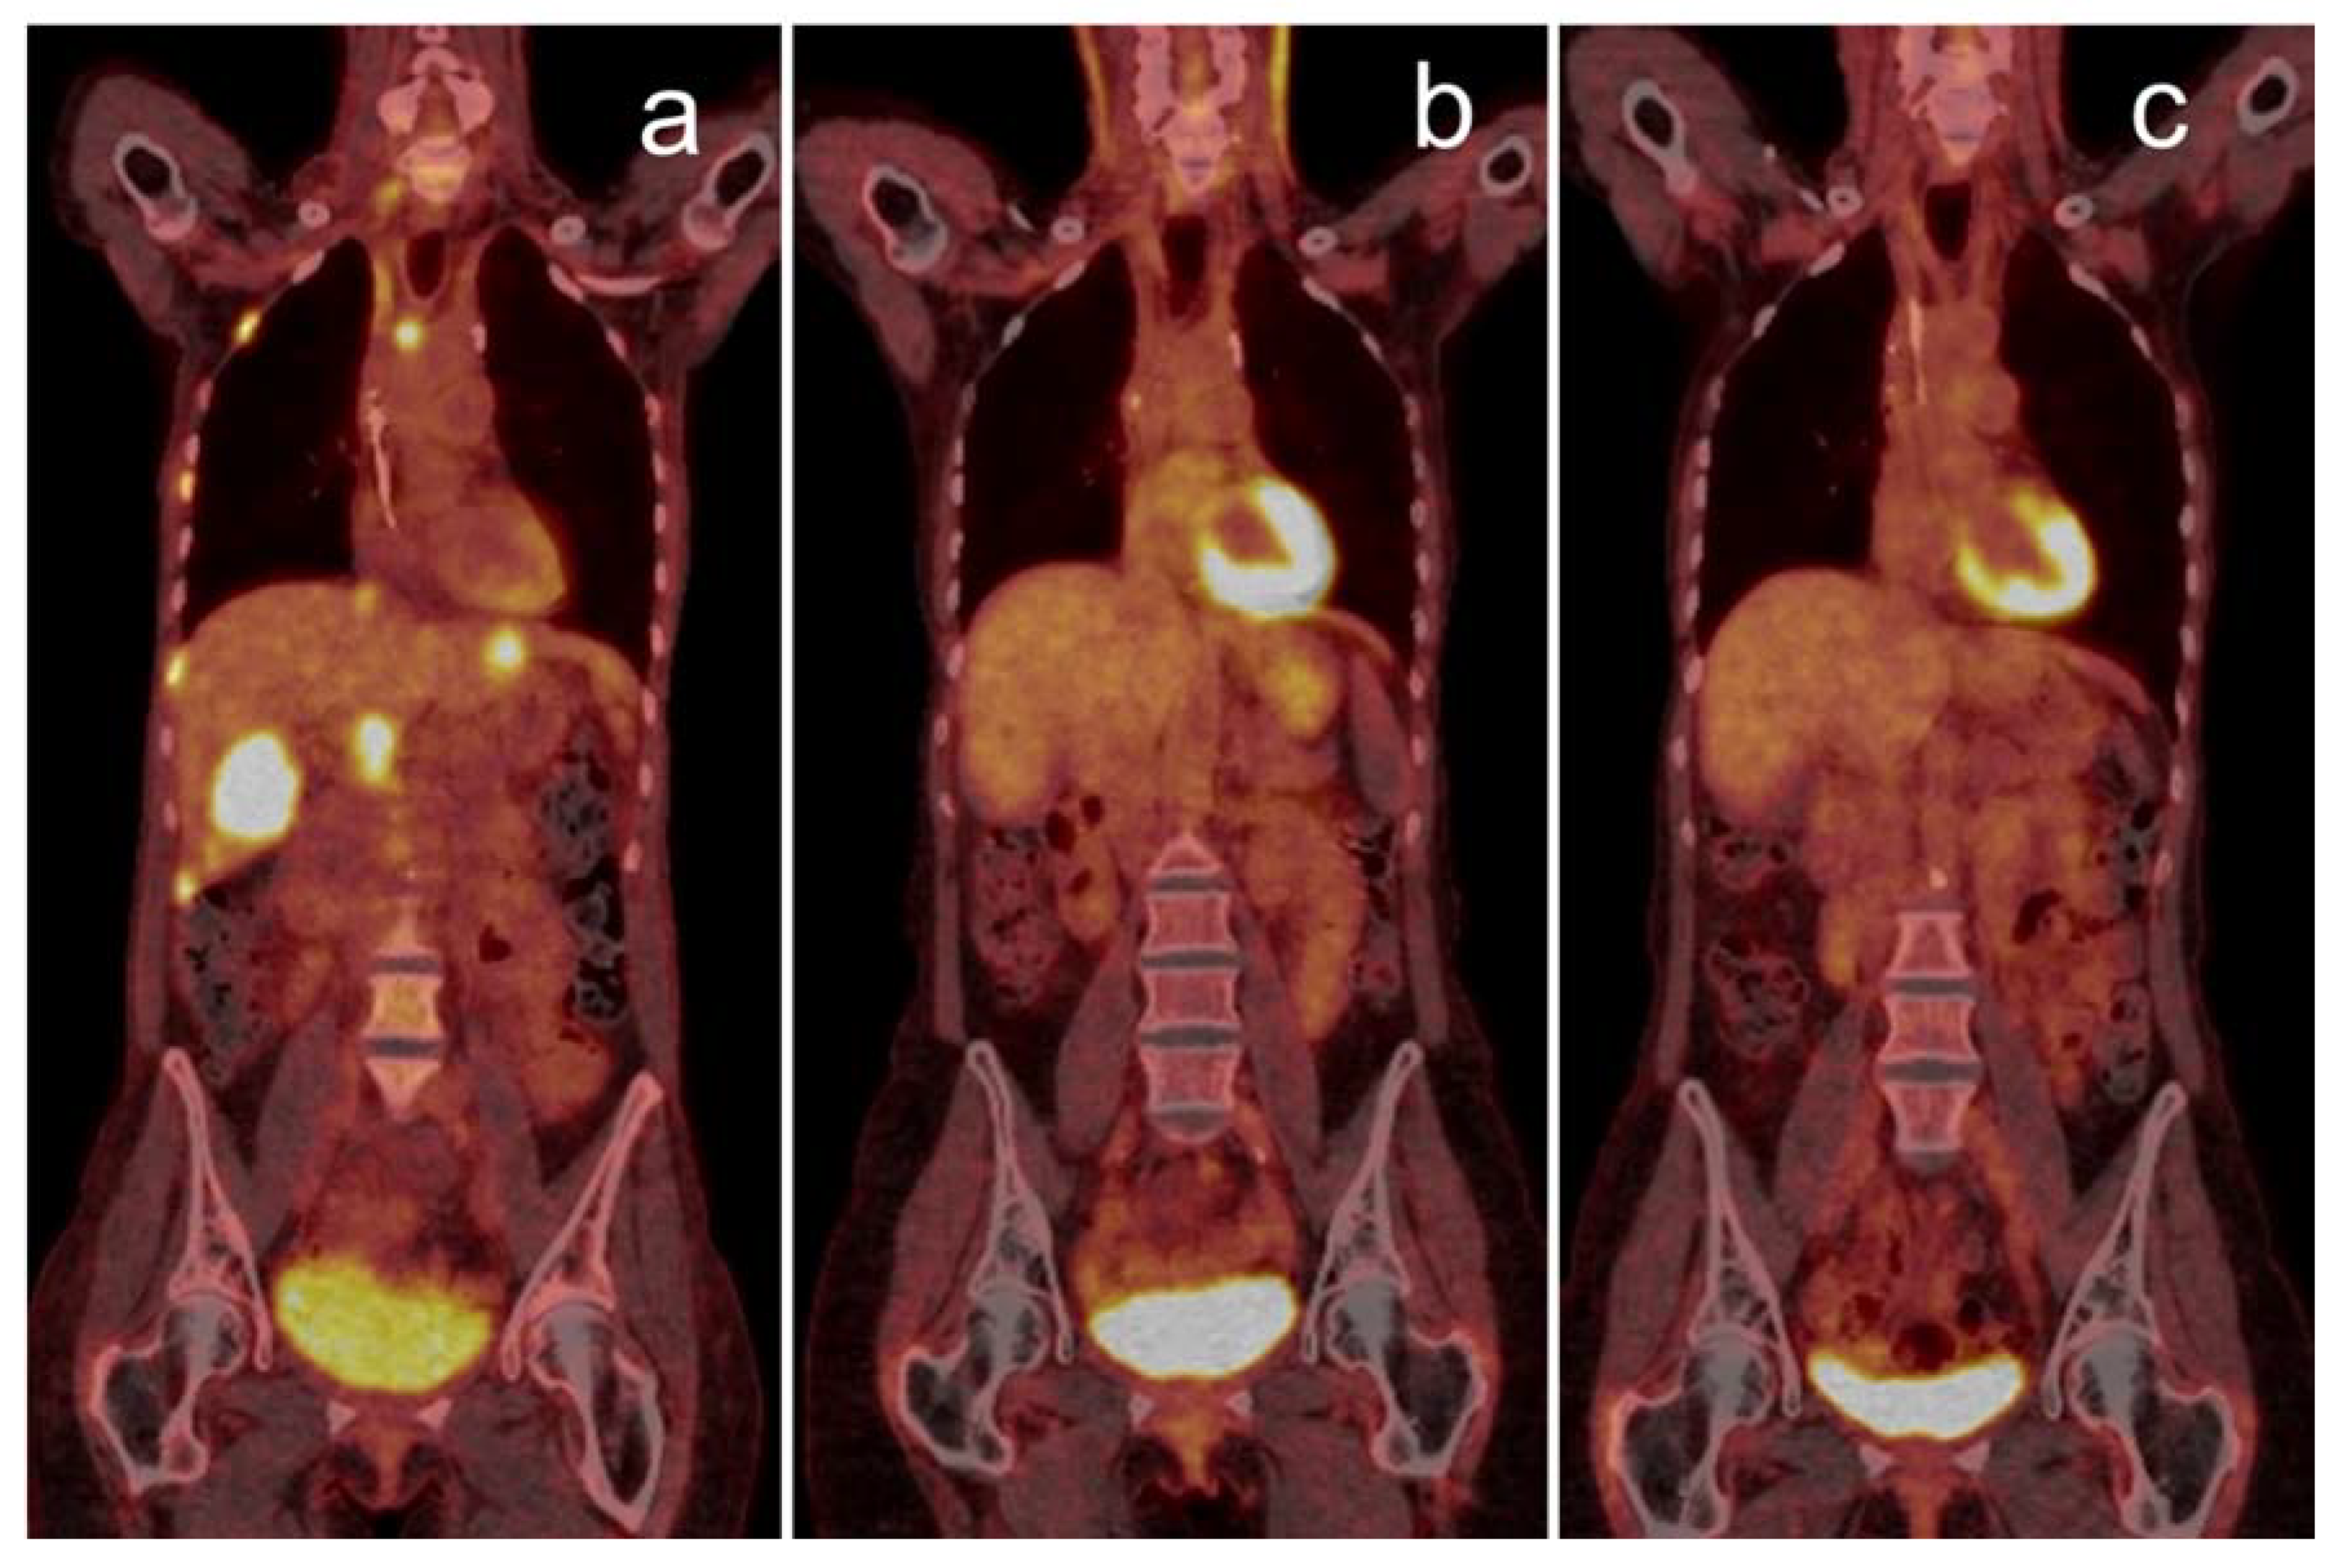

Basic evaluation of therapy response using PET/CT can be accomplished using qualitative parameters, like the decrease or increase in metabolic of active tumor lesions. Such binary “good or poor” categorization is rather robust and can be used, e.g., for end-of-treatment assessment. Particularly complete metabolic response in PET represents an important individual decision-making criterion and generally indicates a favorable long-term outcome [19]. An example of such positive sustained response is shown in Figure 1. Similarly, the appearance of new lesions in follow-up is of higher clinical relevance than changes in preexisting lesions [20].

Figure 1.

Complete metabolic response over two years visualized by PET/CT: 68-year-old woman with stage IV lung squamous-cell carcinoma (PD-L1 1%) having progressed after first-line chemotherapy, showing multiple liver, bone and lymph node metastases (a). The patient responded well to pembrolizumab monotherapy, with a PET/CT follow-up scan after one year (b) showing complete metabolic remission. Therapy was completed after two years, still in complete metabolic remission (c). PET/CT: positron emission tomography/computed tomography; PD-L1: programmed death-ligand.

Durable responses to ICI therapy are not comprehensively defined but can occur both after primary partial or complete remission or out of stable disease [25]. As shown in Figure 1, 18F-FDG PET/CT can be used to determine long-term remission also on the metabolic level.